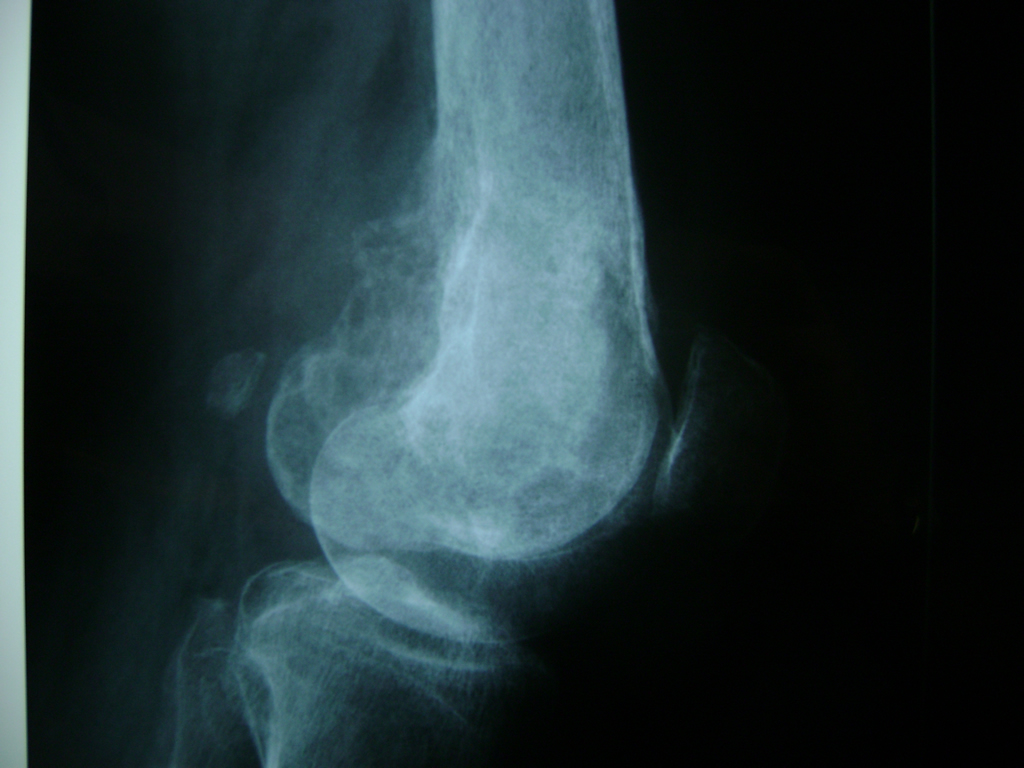

Fémur - Rodilla